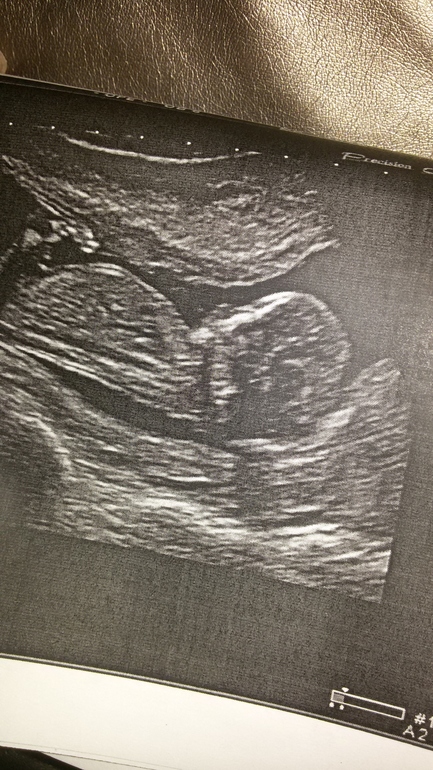

Сегодня сделал первое УЗИ!

Результаты: УЗИ, КТГ, доплера, скринингаПервое за беременность)Срок прям ровно 14 недель ,как и по менструации😊Плацента по передней стенке,что удивило)И у нас ДЕВОЧКА!!!Боже ,как же я рада,как же я её хотела)

Спасибо) да,я сама увидела что там девуля,потом узистка подтвердила и показала что ничего там не от растёт))